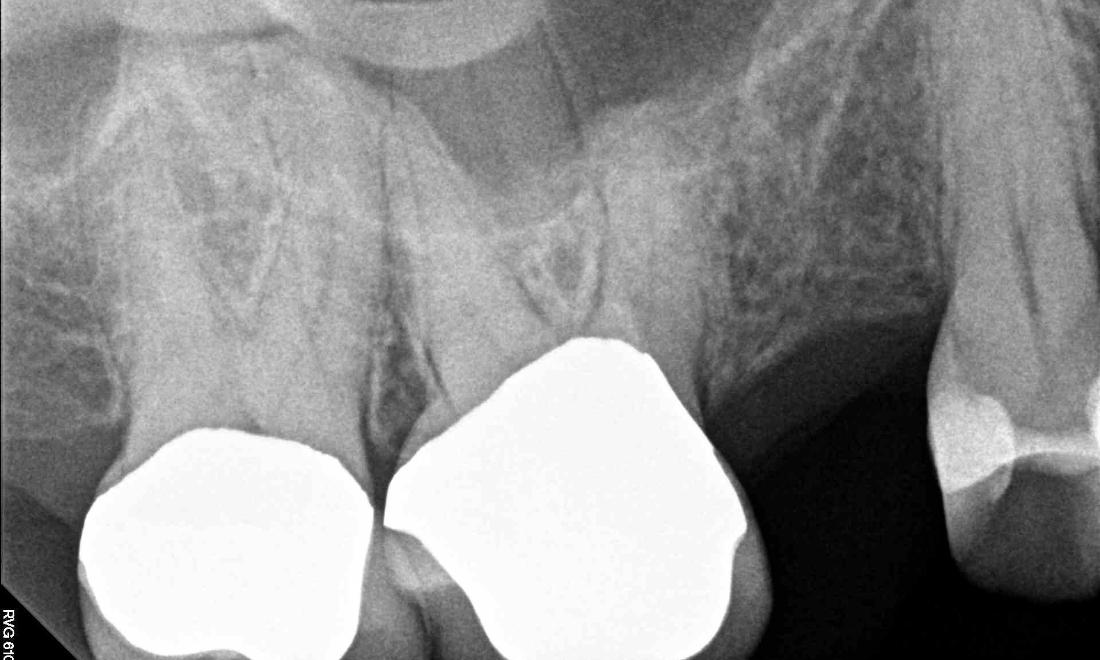

This wonderful patient came to us all the way from Colorado to have a dental implant done. At her first evaluation appointment, an x-ray was taken and Dr. Jordan determined that a minor sinus lift was needed to allow room for a dental implant. The sinus lift and insertion of the dental implant went perfectly! After healing, a tooth colored crown was placed on top of the implant and as you can see, it looks very life-like. She was very pleased.